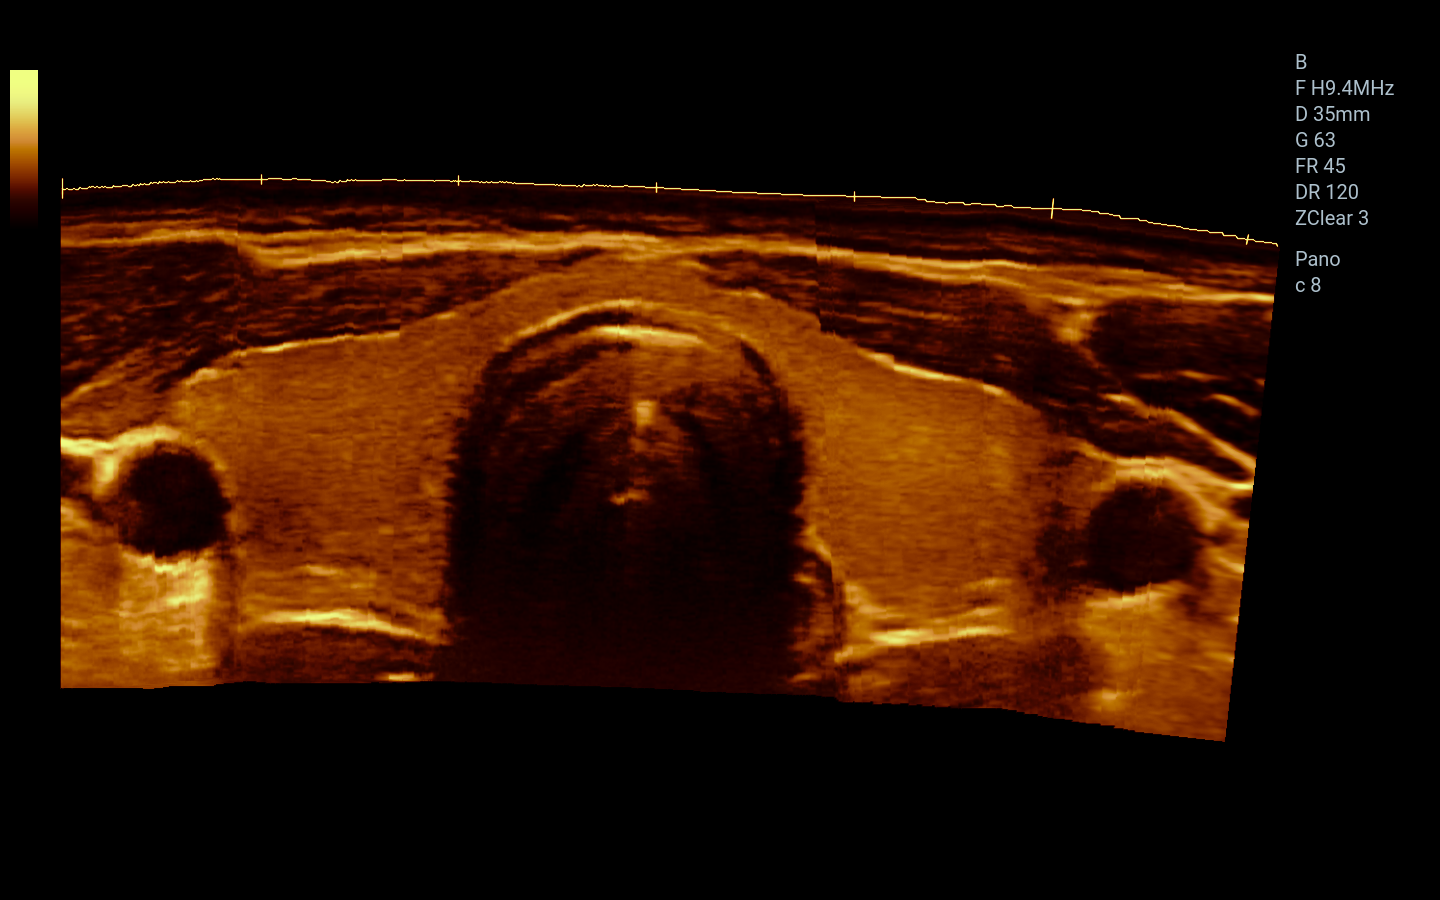

Órganos pequeños / Superficiales

Ortopedia, MSK, Nervio

Lineal

Panorámico y Color Panorámico (EFOV)

Imágenes clínicas extraordinarias